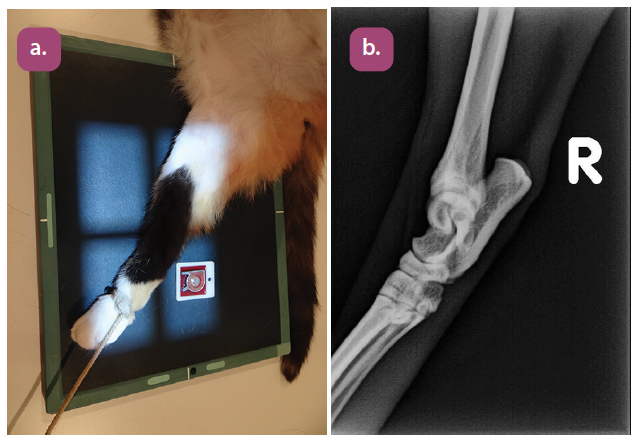

mediolateral projection of the elbow

craniocaudal projection of the elbow

flexed mediolateral projection of the elbow